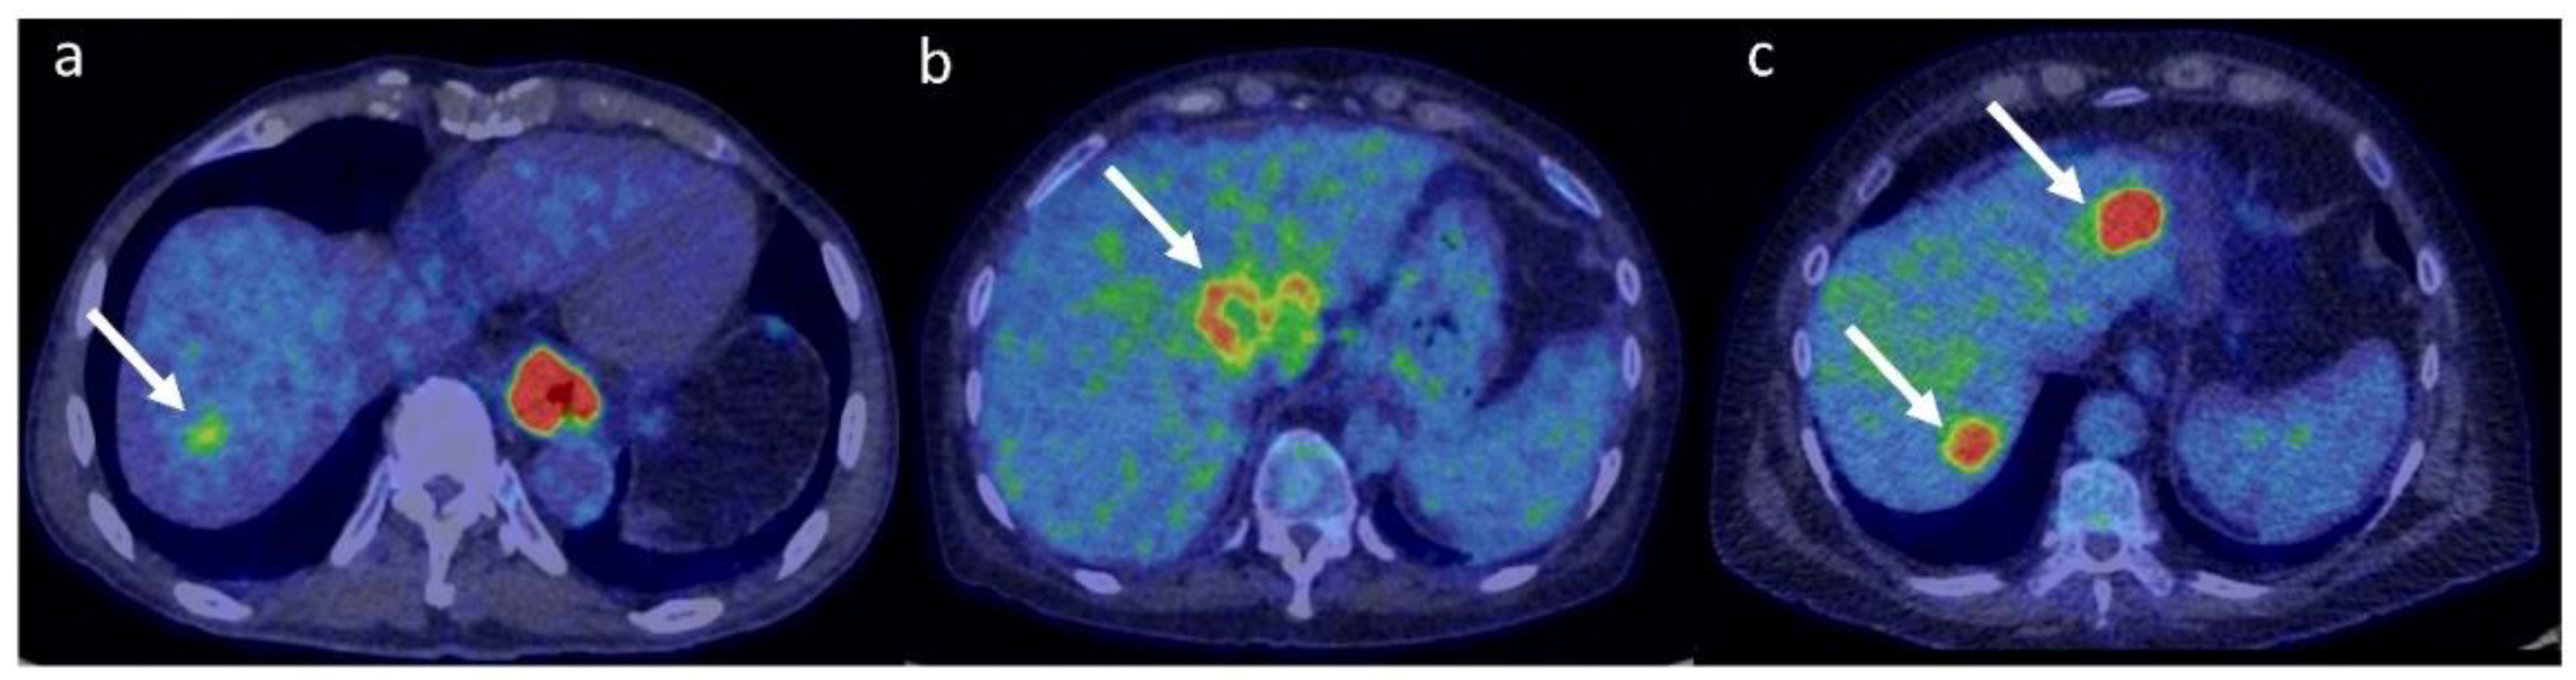

- Ho, C.-L.; Yu, S.C.H.; Yeung, D.W.C. 11C-acetate PET imaging in hepatocellular carcinoma and other liver masses. J. Nucl. Med. 2003, 44, 213–221. [Google Scholar] [PubMed]

- Hwang, K.H.; Choi, D.-J.; Lee, S.-Y.; Lee, M.K.; Choe, W. Evaluation of patients with hepatocellular carcinomas using [11C] acetate and [18F] FDG PET/CT: A preliminary study. Appl. Radiat. Isot. 2009, 67, 1195–1198. [Google Scholar] [CrossRef] [PubMed]

- Cheung, T.T.; Ho, C.L.; Lo, C.M.; Chen, S.; Chan, S.C.; Chok, K.S.H.; Fung, J.Y.; Chan, A.C.Y.; Sharr, W.; Yau, T.; et al. 11C-acetate and 18F-FDG PET/CT for clinical staging and selection of patients with hepatocellular carcinoma for liver transplantation on the basis of milan criteria: Surgeon’s perspective. J. Nucl. Med. 2013, 54, 192–200. [Google Scholar] [CrossRef]

- Park, J.-W.; Kim, J.H.; Kim, S.K.; Kang, K.W.; Park, K.W.; Choi, J.-I.; Lee, W.J.; Kim, C.-M.; Nam, B.H. A prospective evaluation of 18F-FDG and 11C-acetate PET/CT for detection of primary and metastatic hepatocellular carcinoma. J. Nucl. Med. 2008, 49, 1912–1921. [Google Scholar] [CrossRef]